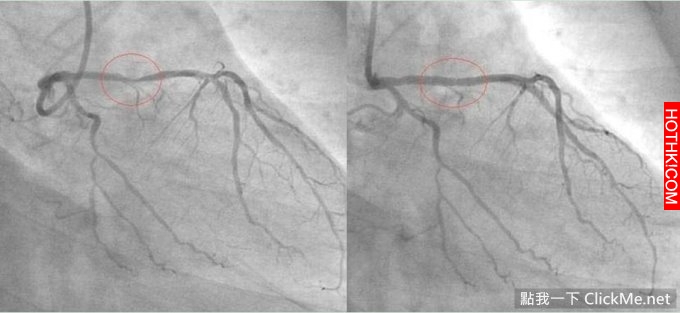

當血管堵塞不足70%時,人體無任何感覺,當堵塞超過70%進入晚期時,人體才會有不良感覺。

按照血管橫斷堵塞的程度,一般分為:

堵塞初期:堵塞30%無癥狀

堵塞中期:堵塞達50%無癥狀

堵塞晚期:堵塞達70%出現癥狀